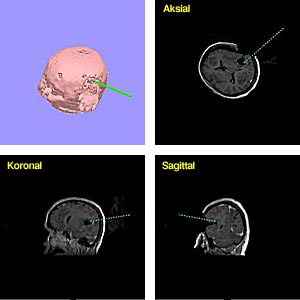

Ultralyd, MR og CT kan også gi tredimensjonale data (3D). Fortsatt er hastigheten ved 3D-avbildning så lav at systemet ikke kan benyttes interaktivt. Men 3D-funksjonen kan benyttes preoperativt i planleggingen av en intervensjon, intermitterende under en operasjon (fig 2) eller ved programmering av en robot (5, 6).

Forhåndsprogrammerte roboter er også brukt ved stereotaktisk intrakranial kirurgi. Den nevrokirurgiske roboten MINERVA (Swiss Federal Institute of Technology of Lausanne, Sveits) (6) er utviklet for å operere i en CT-skanner. Roboten er forhåndsprogrammert og utfører hele inngrepet, kirurgens rolle er å planlegge og overvåke prosedyren. En annen stereotaktisk robot er NEUROMATE fra iMMi Medical Robots (Bron, Frankrike). Her er det instrumentføringen ved f.eks. biopsier som forhåndsprogrammeres, slik at guiden til biopsinålen er nøyaktig posisjonert og orientert før biopsien utføres manuelt.